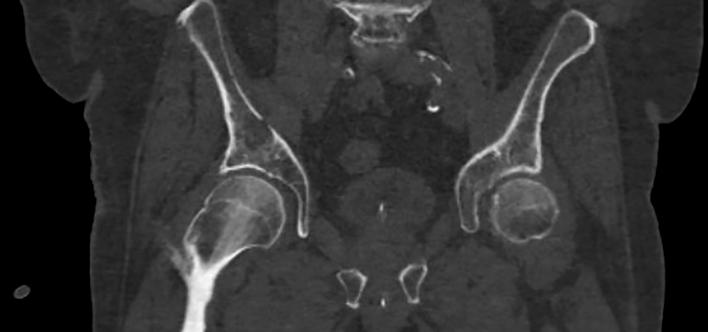

HNE: Roði í slímhimnu (conjunctiva) og hvítu (sclera) sem náði ekki að glærubrún (mynd 1A). Þroti í kringum augu en enginn gröftur. Ekki hor í nösum eða roði í hálsi en lítil blaðra á innanverðri kinn hægra megin. Varir þrútnar, rauðar, þurrar og sprungnar (mynd 1B).Hvít skán á bólginni tungu (mynd 1C).Eitlastækkanir beggja vegna á hálsi. Hjarta og lungu:Hjartahlustun eðlileg.Radialis púlsar sterkir og reglulegir. Lungnahlustun hrein.Góð háræðafylling.  Kviður: Mjúkur og eymslalaus. Húð: Mikið af rauðum blettóttum útbrotum ílófumogáiljumþarsemþauvorueinnigorðin samfelld (confluent) (mynd 1D). Hringlaga og markskífulaga (targetoid) ljósrauð blettótt útbrot á bringu, baki, fótleggjum og kvið og í holhönd og nára. Mismunandi að stærð frá nokkrum mm uppí 2-3 cm.

Mynd 1. Einkenni við komu á bráðamóttöku. (A) Roði í slímhimnu og hvítu sem náði ekki að glærubrún. (B) Þurrar og sprungnar varir. (C)

Hvít skán á bólginni tungu. (D) Blettótt, samfelld, markskífulaga útbrot.